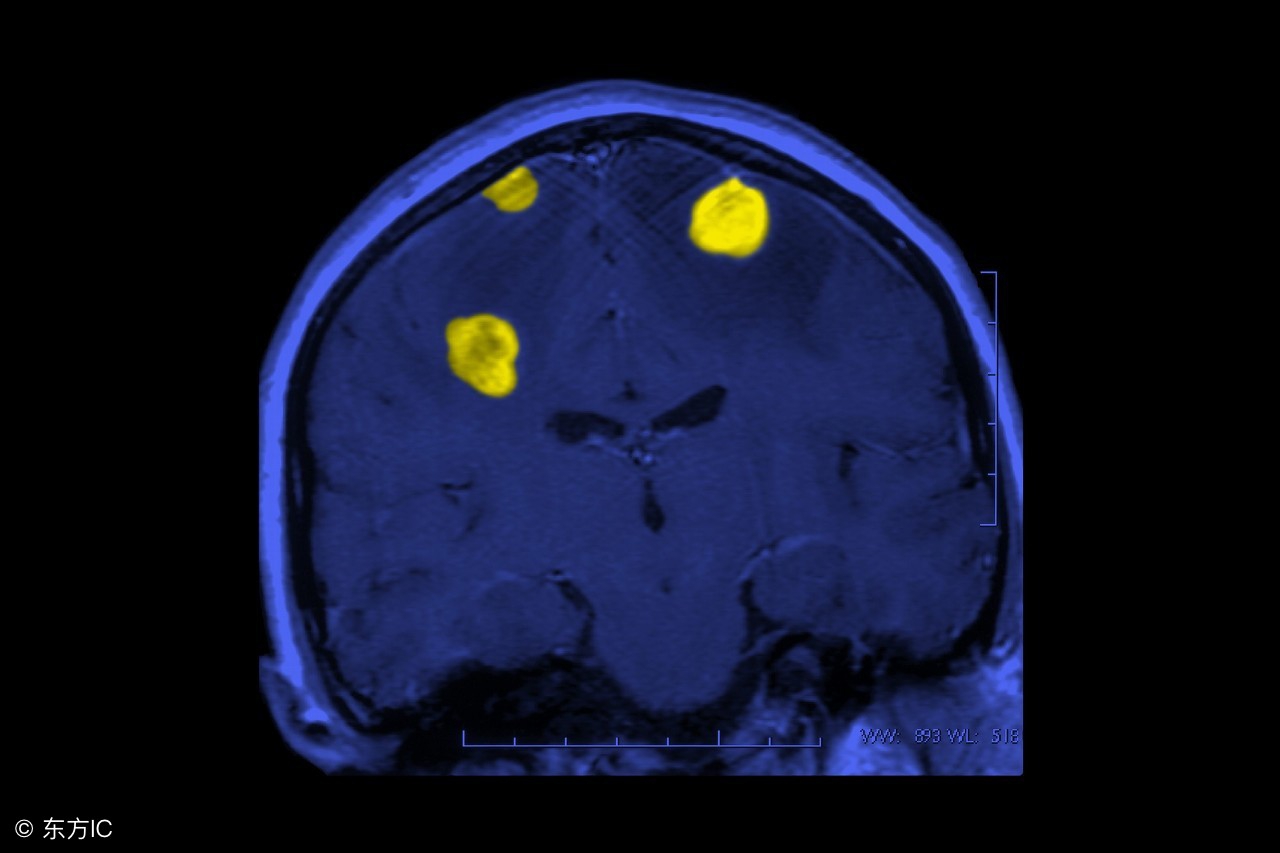

适应症 :治疗体积小,1-30cm³, 直径小于4cm,病灶数小于3个 ( 选择此项技术重点:小体积病灶 )。